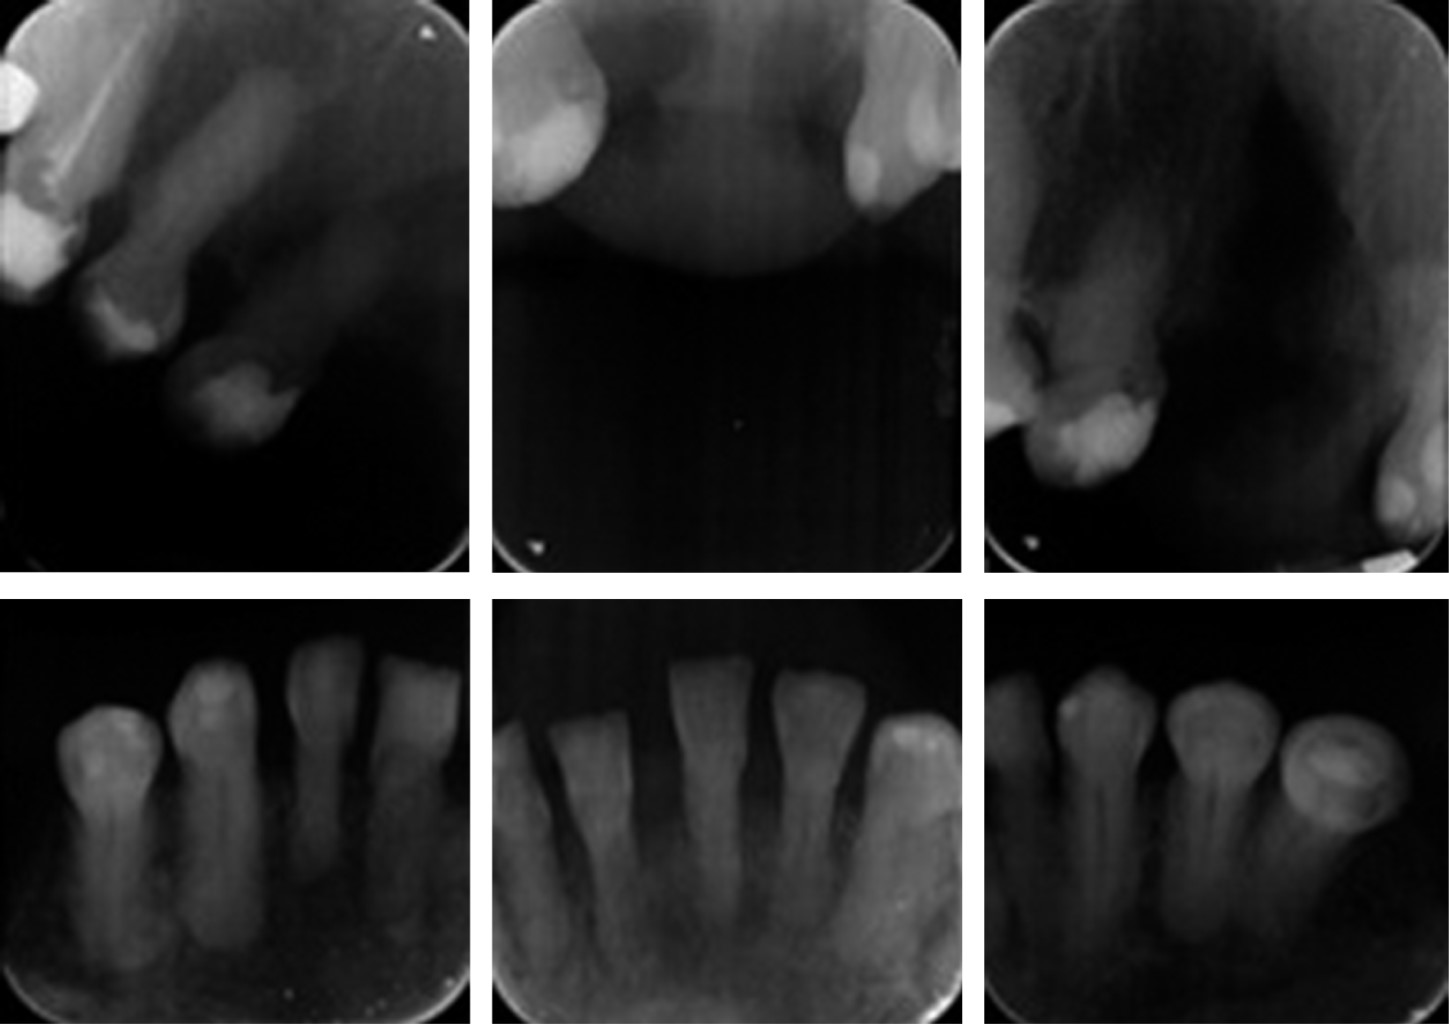

Se procede a realizar el diagnóstico intraoral de la paciente con el apoyo de radiografías periapicales y ortopantomografía, así como modelos de yeso. Valoración por las especialidades de periodoncia, cirugía, prótesis y endodoncia.

Radiográficamente se observó anodoncia parcial, caries y restauraciones defectuosas/mal adaptadas, pérdida de hueso horizontal y/o vertical en todos los sextantes, cráteres óseos, paladar hendido, hipercementosis en todos los dientes, raíces enanas, fracturas coronarias, seno y membrana maxilar pequeña, alteración de la articulación temporomandibular y restos radiculares (Figuras 2 y 3).

Figura 3